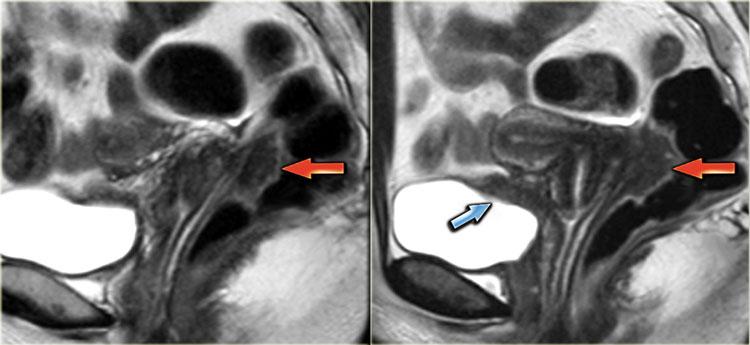

Hình ảnh T2W mặt phẳng đứng dọc này cho thấy lạc nội mạc tử cung xâm lấn sâu tại túi cùng sau với xâm lấn thành trực tràng.

Hình ảnh T2W của lạc nội mạc tử cung xâm lấn torus uterinus.

Hình ảnh T2W cho thấy lạc nội mạc tử cung xâm lấn sâu tại vòm âm đạo sau và torus uterinus.

Không có xâm lấn thành ruột.

Hình ảnh chuỗi xung T2W minh họa sự xâm lấn dây chằng tử cung-cùng bên trái.